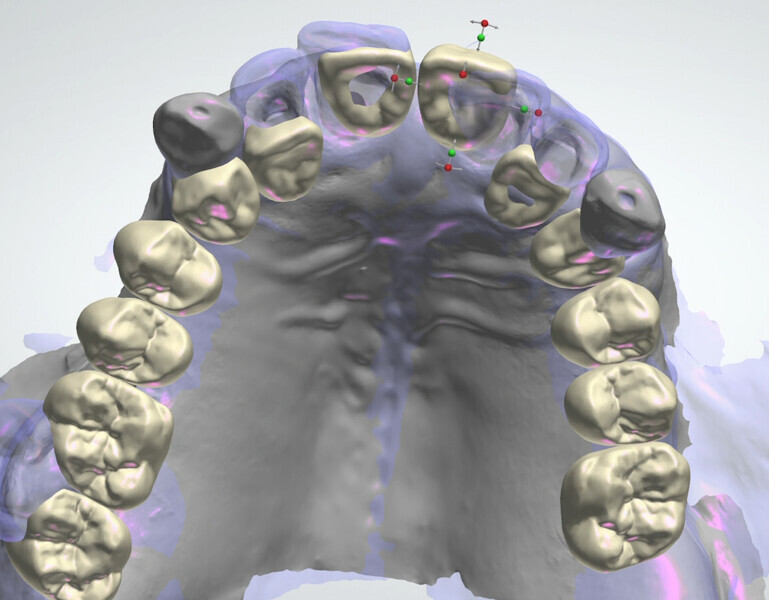

The fully digital Pro Arch protocol